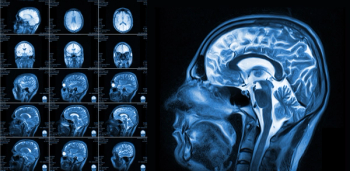

Utilizing susceptibility-weighted magnetic resonance imaging (MRI) in a study involving over 20,700 people, researchers found that drinking more than seven units (56 grams) of alcohol a week led to a higher accumulation of brain iron, which can trigger cognitive decline.